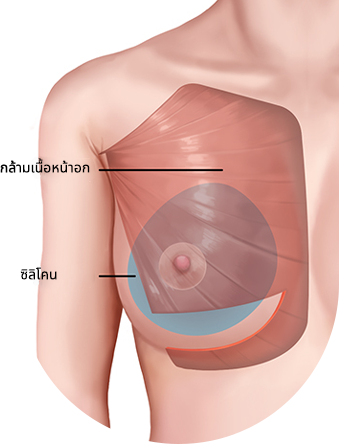

ใส่ซิลิโคนระหว่างกล้ามเนื้อที่ถูกกรีด ส่วนบนของซิลิโคนอยู่ด้านล่างของกล้ามเนื้อหน้าอก ส่วนล่างของซิลิโคนอยู่ด้านบนของกล้ามเนื้อหน้าอก

วิธีการใส่ท่อนบนของซิลิโคนลงไปใต้กล้ามเนื้อ และท่อนล่างลงไปใต้เยื่อกล้ามเนื้อ

มักจะใช้กล้ามเนื้อปิดเนื้อเยื่อบางๆของผิวหนัง เพื่อให้เห็นซิลิโคน และความกังวลน้อยลง

เนื่องจากความกดดันของกล้ามเนื้อ จึงมีความเสี่ยงน้อยที่ตำแหน่งของซิลิโคนจะเคลื่อนที่ได้ และความน่าจะเป็นที่จะเกิดคลื่นริ้วรอยก็มีน้อยด้วย

บริเวณที่มีกล้ามเนื้อจะมีผิวหนังและเนื้อเยื่ออ่อนที่ยืดไม่ค่อยออก แต่บริเวณที่ไม่มีกล้ามเนื้อปกคลุมนั้นค่อนข้างที่จะ

ผิวหนังและเนื้อเยื่อที่เชื่อมต่อกันจะยืดได้ดีและช่วยให้เส้นโค้งธรรมชาติยังคงอยู่แม้ในกรณีที่ด้านล่างของหน้าอกแน่นมาก

วิธีการใส่ซิลิโคนบนกล้ามเนื้อ ,ใส่ซิลิโคนใต้เนื้อเยื่อ

เป็นวิธีการผ่าตัดที่เสริมข้อเสียของวิธีใช้สายเดรนและวิธีใช้กล้ามเนื้อ และรวมข้อดีเข้าด้วยกัน

เป็นวิธีการผ่าตัดสามารถสร้างรูปร่างตามธรรมชาติได้

ไม่เหมาะสำหรับเนื้อเยื่อใต้ผิวหนัง (ไขมัน) น้อย

ส่วนที่มีกล้ามเนื้อจะไม่ค่อยยืดออก